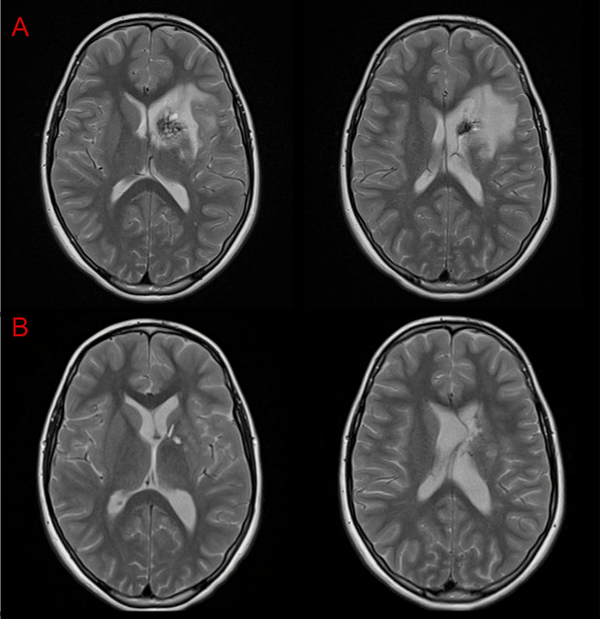

Otra vía considerada fue el abordaje transfrontal mediante el uso de la técnica “tubular”7 o mediante corticotomía; ambas permitirían acceder al Cavernoma en forma directa pero con la posibilidad de no abarcarlo en su totalidad o incidir inadvertidamente las fibras de la CI. Aunque la elocuencia del tejido a nivel frontal es menor y toleraría mejor las maniobras de retracción necesarias, consideramos que ese corredor quirúrgico también sería estrecho. Nos inclinamos por la vía interhemisférica contralateral por considerar que el sangrado previo según se evidencia en la RMI (Figura 6) había delineado una vía de acceso que evitaría realizar una nueva incisión sobre el tejido sano interpuesto.

Figura 6: RMI A- Preoperatoria. B- Control posoperatorio a las 24hs.